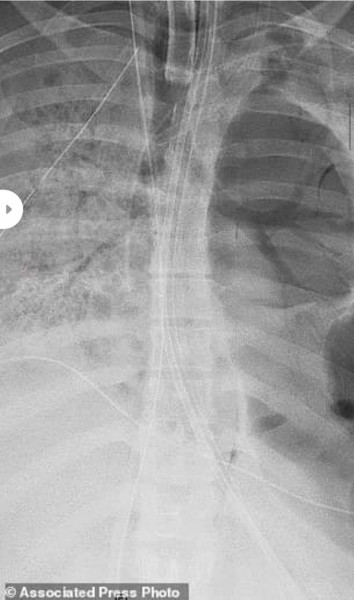

صور صادمة لرئة فتاة تعافت من (كورونا).. كيف تصرف الأطباء؟

نشرت صحيفة "ديلي ميل" البريطانية صورًا صادمة لرئة لفتاة إسبانية تعافت من فيروس كورونا، إذ أُجري لها عملية جراحيه دقيقة لاستبدالهما كي تتمكن من العيش بطريقة طبيعية.

وقال الدكتور أنكيت بهارات استشاري أمراض الرئة والرعاية الحرجة، إن اجراء العملية استمر لمدة 10 ساعات لأن الفيروس ترك رئتيها مملوءتين بالثقوب وكاد يقترب من جدار القفص الصدري، وأن هذه العملية هي فرصتها الوحيدة في البقاء.